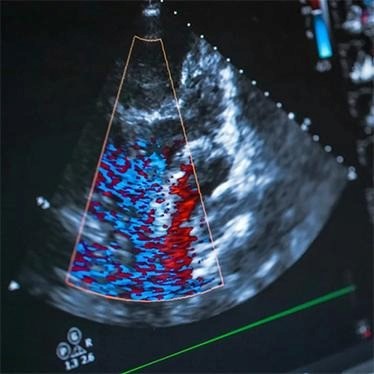

اکو قلب

اکوکاردیوگرافی در خانه؛ پکیج تخصصی و تشخیصی فوری

پکیج اکوکاردیوگرافی دایان سلامت شامل مجموعه‌ای از خدمات تخصصی اکو قلب در منزل است که به‌صورت یکپارچه و توسط پزشکان متخصص قلب ارائه می‌شود. این خدمت تخصصی اغلب همراه با ویزیت متخصص قلب در منزل صورت می‌گیرد تا وضعیت پمپاژ، ساختار دریچه‌ها و ابعاد حفره‌های قلبی، دقیق ارزیابی شود. این رویکرد چندجانبه به پزشک کمک می‌کند تا در همان جلسه ویزیت، تفسیر کاملی از نتایج را به خانواده بیمار ارائه دهد و در صورت نیاز برای تغییر دارو یا مداخلات درمانی، بلافاصله تصمیم‌گیری کند.

• انجام اکوکاردیوگرافی با دستگاه پرتابل مجهز و پیشرفته

کیفیت اکوکاردیوگرافی با دستگاه‌های پرتابل در منزل مشابه مراکز درمانی است؟

بله. تجهیزات مورد استفاده در اکو قلب در خانه توسط دایان سلامت از پیشرفته‌ترین مدل‌های پرتابل هستند که دقت تشخیصی مشابه دستگاه‌های ثابت بیمارستانی دارند.